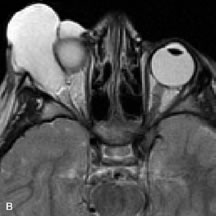

Metastatic Tumors

Breast carcinoma metastatic to the orbit has been demonstrated to be hypointense to the surrounding orbital fat on T1-weighted studies and hyperintense on T2-weighted images and has an affinity to the extraocular muscles (Fig. 20).50,64 The MRI characteristics of prostate carcinoma metastatic to the orbit have been described as involving the greater and lesser wing of the sphenoid, orbital roof, and optic canal. Diffuse bone hypertrophy with isointense or slightly hyperintense tissue on T1-weighted images represents the osteoblastic carcinomatous bone infiltration. Contrast enhancement is variable on T1-weighted and fat-suppressed images.65

Fig. 20. A. T1-weighted MR scan demonstrates nodular enlargement of both medial rectus muscles (arrows). B. T1-weighted fat-suppressed contrast-enhanced scan confirms the presence of small metnstatic deposits within the muscles (open arrows).